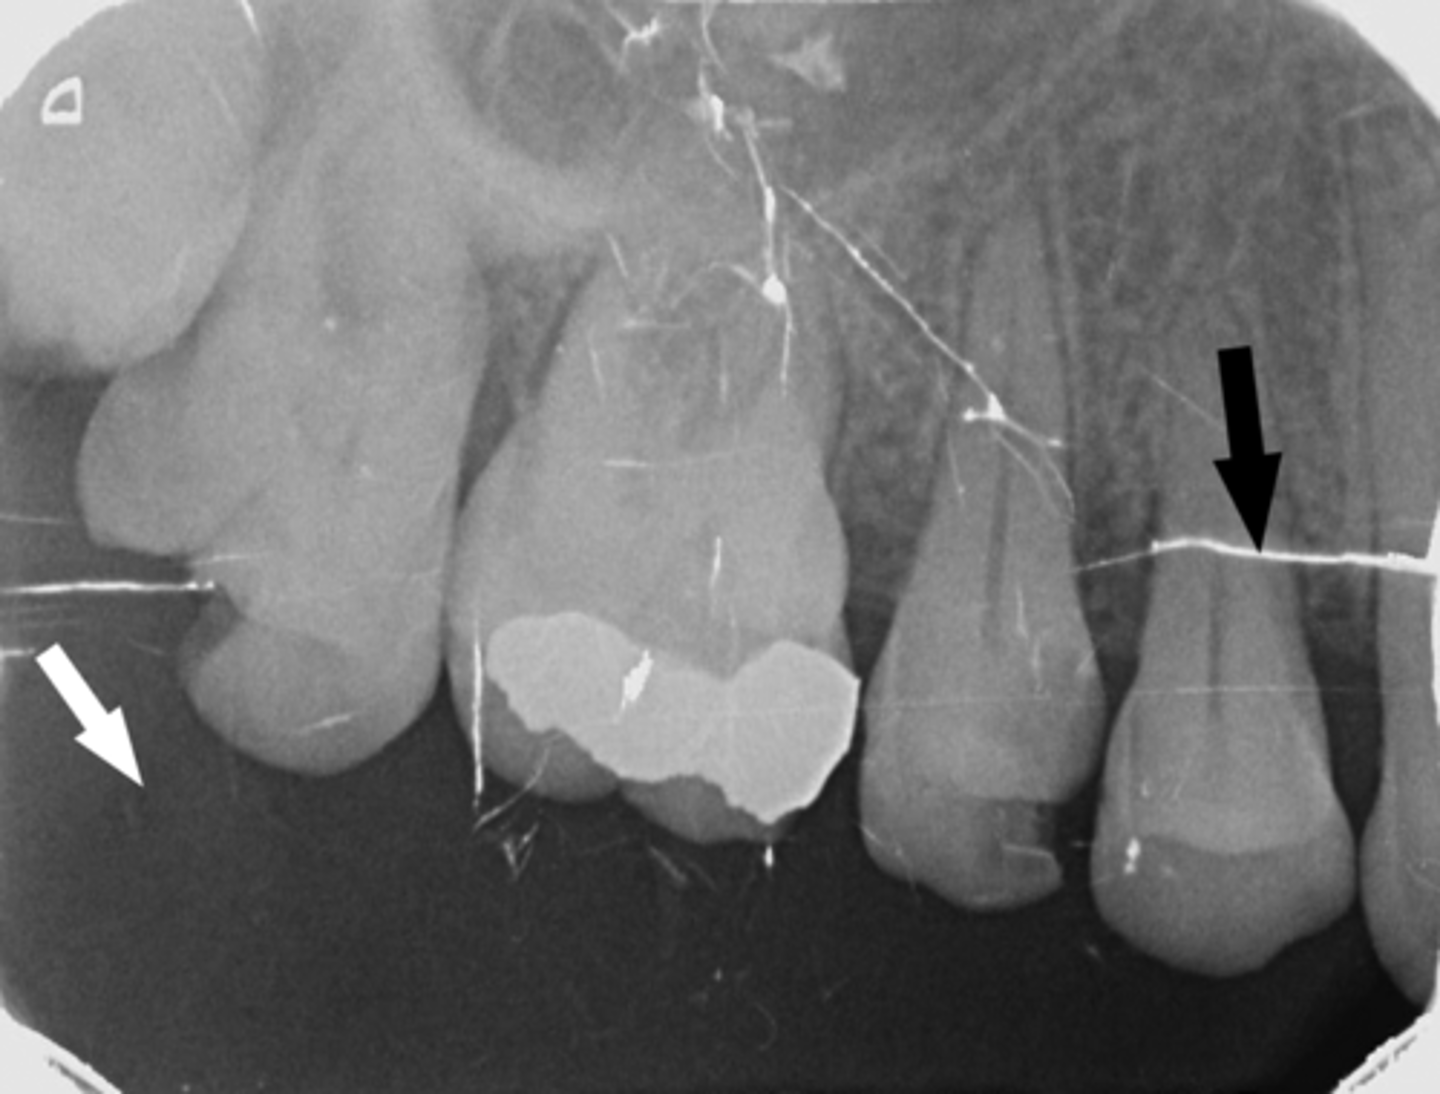

Incorrect Horizontal Angulation

-Overlapped contacts

-CR was not directed through the interproximal spaces, resulting in the proximal surfaces of adjacent teeth appear overlapped in the PA.

-Occurs in both paralleling and bisecting technique

-To prevent direct the x-ray beam through the interproximal regions

Incorrect Horizontal Angulation -->Bite-Wing

-CR was not directed through the interproximal spaces.